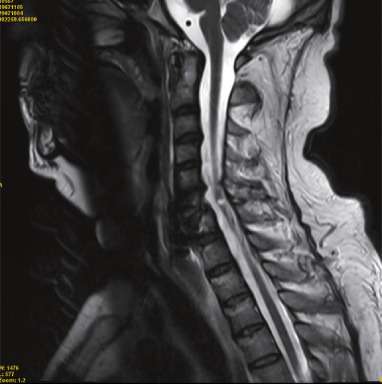

La polineuropatía idiopática aguda, más conocida como síndrome de Guillain-Barré, es una afección neurológica de inicio súbito o subagudo que se caracteriza por una disfunción progresiva del sistema nervioso periférico.…